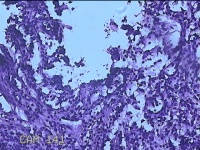

右侧手掌肉芽组织

性别

女

年龄

48岁

临床诊断

手掌开放性损伤

一般病史

右侧手掌肉芽组织增生

标本名称

大体所见

灰白暗红色带皮肤样组织1.3x0.8x0.3cm一块,切面灰白粉红色,质软。